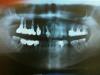

Ashhh Опубликовано 27 августа, 2012 Автор Поделиться Опубликовано 27 августа, 2012 Посмотрите, пжл, как видно? Ссылка на комментарий

Bier Опубликовано 27 августа, 2012 Поделиться Опубликовано 27 августа, 2012 вы снимок неправильно повернули. Там слишком близко друг к другу 2 имплантата, между ними ушла кость, образовался карман. Отсюда и боли. Ссылка на комментарий

Ashhh Опубликовано 28 августа, 2012 Автор Поделиться Опубликовано 28 августа, 2012 А может такая расстановка из-за снимка быть, просто я помню, что эти два как раз далеко от друг-друга должны были (когда ставил, он мне говорил, что вместо 5-го и 7-го ставит). Или основание у них сблизились? Ссылка на комментарий

Bier Опубликовано 28 августа, 2012 Поделиться Опубликовано 28 августа, 2012 я бы снял коронки и удалил 1 имплантат. Ссылка на комментарий

Bier Опубликовано 28 августа, 2012 Поделиться Опубликовано 28 августа, 2012 да, я бы убрал средний имплантат и оставил мост на двух. Ссылка на комментарий